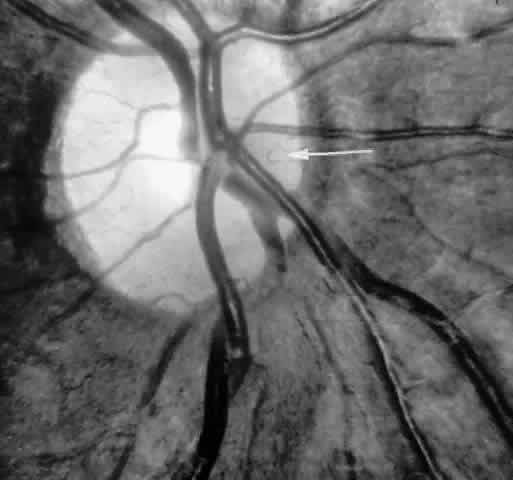

The occluded arterioles may be invisible or may have a “silver-wire” or chalk-white appearance, as first described by Goodman and colleagues39 (Fig. 21). Fluorescein angiography may demonstrate an abrupt complete occlusion at the interface between peripheral nonperfused and posterior perfused retina. Frequently, this occlusion will take place just distal to a branching vessel, giving the appearance of a freshly pruned rose bush. The nonperfused anterior peripheral retina will have a grayish brown appearance and on fluorescein angiography will appear blurred without clearly defined fundus markings.

Fig. 21. A. Photograph of the peripheral retinal vasculature shows sheathed vessels and absence of peripheral vascular perfusion. B. Fluorescein angiogram shows area of nonperfusion representing stage I sickle cell retinopathy. White arrow points to corresponding vascular bifurcation in A and B.